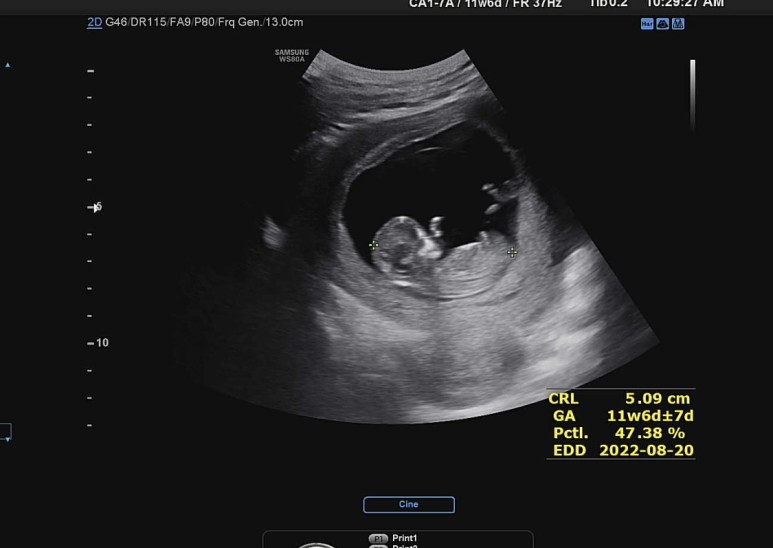

꿀잠이 12주차 머리-엉덩이 길이는 5.09cm

5센치가 넘었구나~ 이 시점부터는 태아가 구부리고 있어 총 길이를 잴 수 없어 머리에서 엉덩이까지의 길이로 크기를 확인한다. 5cm를 손가락으로 가늠해보면서.. 너는 아직 요만하구나 헤헤.